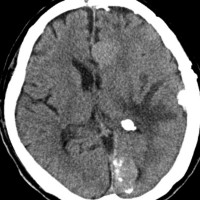

片側髄膜腫症 unilateral meningiomatosis

50歳ころから15年間に3回の開頭手術を受けている患者さんです。parasagittal, falx, convexityなど6個の髄膜腫がすでに摘出されています。左側だけ,テント上だけに髄膜腫が20個くらい多発していました。これらはグレード1で,anaplastic meningiomaの転移ではありません。

やがて蝶形骨縁の髄膜腫の増大速度が早まりatypical meningiomaとなりました。MIB-1 index が10%の高値でした。病理学的にも,psamomatous meningiomaなど様々な種類の髄膜腫が多発しています。

初発時から多発性髄膜腫であり,最初の手術で左側テント上の硬膜を広範囲に摘出しておくべきでした。このような病態は若年者でもみられることがあり,胎生期の硬膜の原基になる細胞にmutationが生じたとしか考えづらいものです。